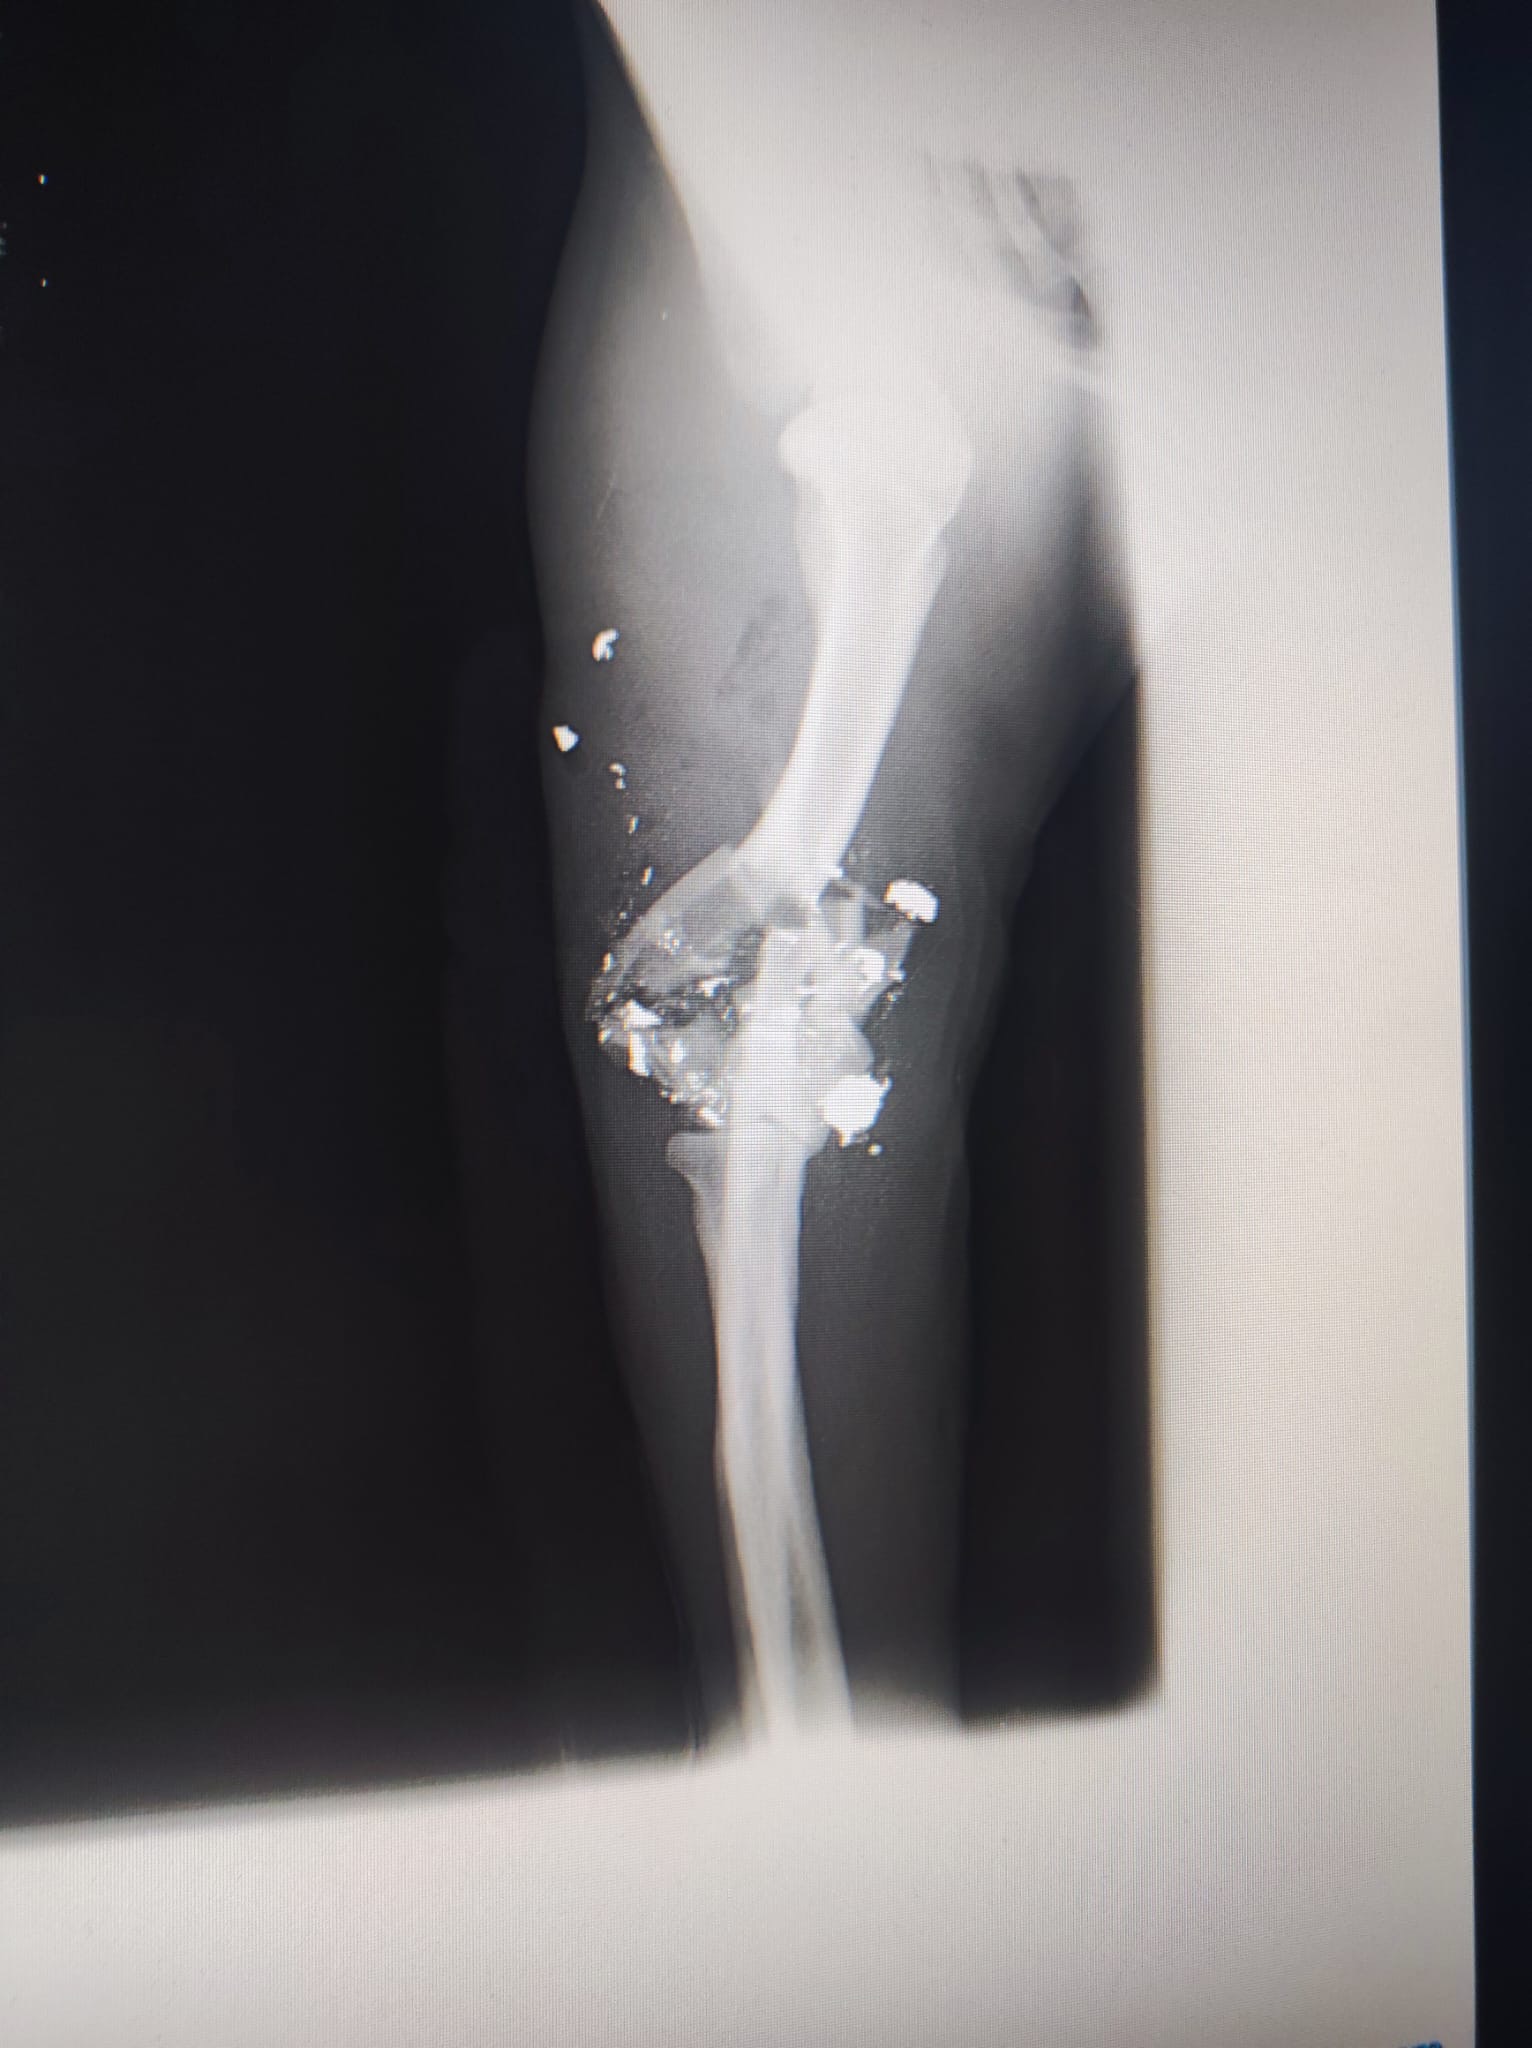

Sonia und Carmen haben einen Beagle mit einem zerschossenen Bein gefunden. Sie sind sofort mit ihm in die Tierklinik gefahren. Der Tierarzt hat einige Splitter und Kugeln aus der Schusswunde am Ellenbogen entfernt. Nun bekommt der Hund Antibiotika, Entzündungshemmer und Schmerzmittel. Eine Operation ist nach dem jetzigen Stand nicht möglich. Freitag findet ein Kontrolltermin in der Klinik statt. Der Beagle ist ein Rüde und lt. Tierarzt ca. sieben Jahre alt, wobei er deutlich älter wirkt. Wir werden weiter berichten. Ein großes Danke wieder einmal an Sonia und Carmen in Galizien.